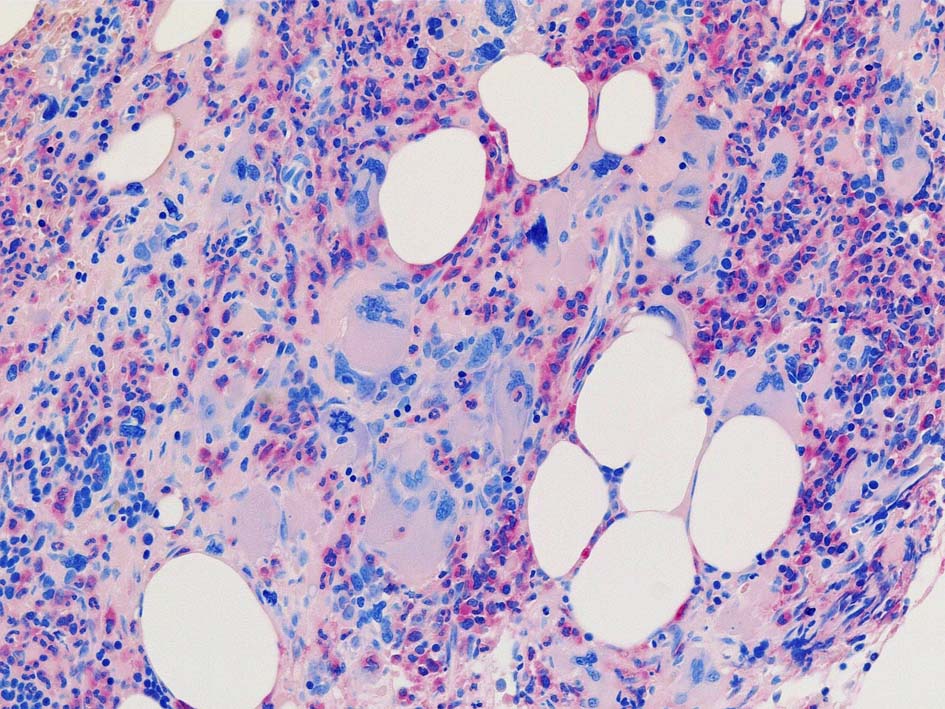

Case02; Meylofibrosis, overt fibrosis

77year-old female. 40歳時polycythemia veraと診断されていた.

黒染する弾性線維の増生のほか, 赤く染まる膠原線維の増生が確認される. MF-2 fibrosis. 鍍銀染色の核染色をすると膠原線維の赤染がわからなくなるので行わない.